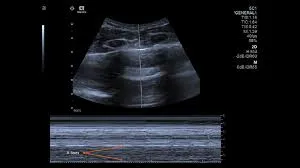

Indian Institutes of Technology, Palakkad, has developed an automated lung ultrasound (LUS) for COVID-19 screening and monitoring through cloud-based image analysis and scoring system.

The app, the first of its kind in India, is now available for clinicians to perform automated analysis by just uploading the ultrasound video.

A nursing assistant (in the absence of a skilled clinician), following a simple protocol of LUS, acquires the lung images and transfers the images to the cloud.

The images are analysed over the cloud and scores are assigned according to certain criteria either for the type of infection or its severity.